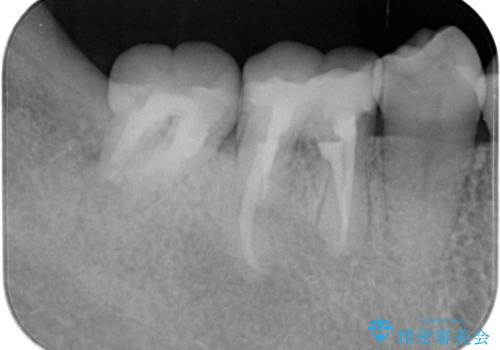

金属のクラウンは薄く加工しても壊れないことがメリットですが、セラミッククラウンを装着するにはスペースが少なすぎ、このまま治療を進めると外れやすく壊れ易いセラミッククラウンの設計となるため、歯周外科を行い狭小なスペースの拡大を行うこととしました。

なんとかギリギリのスペースを確保するこおtができ、無事銀歯を外してセラミック治療を行うことができました。